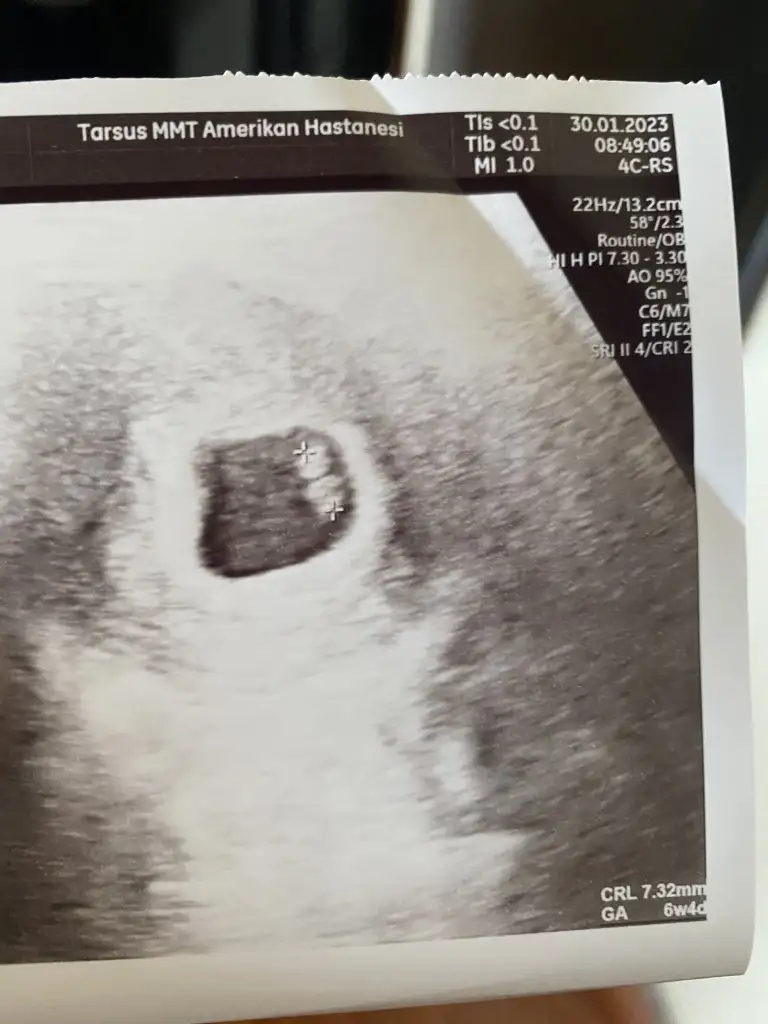

Canım banada yorum yapar mısın 6+4 haftalık karından ultrasonIyi aksamlar haberlerinizi bekliyorum :)

Benimki gibi her tarafı parlak kesenin plasentayi böyle olunca asla göremiyorumCanım banada yorum yapar mısın 6+4 haftalık karından ultrason

Merhaba 6hafta olur muKızlar ultrason fotolarınızı atın 6 ve 7.hafta ya da 11. 12. 13. Hafta yorumlayayim. Amacım kesin bilmek değil net bi şey söyleyemem ancak ultrason net olursa daha iyi olur :)

Kızlar ultrason fotolarınızı atın 6 ve 7.hafta ya da 11. 12. 13. Hafta yorumlayayim. Amacım kesin bilmek değil net bi şey söyleyemem ancak ultrason net olursa daha iyi olur :)

İlki vajinal muayene 6 +4Kızlar ultrason fotolarınızı atın 6 ve 7.hafta ya da 11. 12. 13. Hafta yorumlayayim. Amacım kesin bilmek değil net bi şey söyleyemem ancak ultrason net olursa daha iyi olur :)